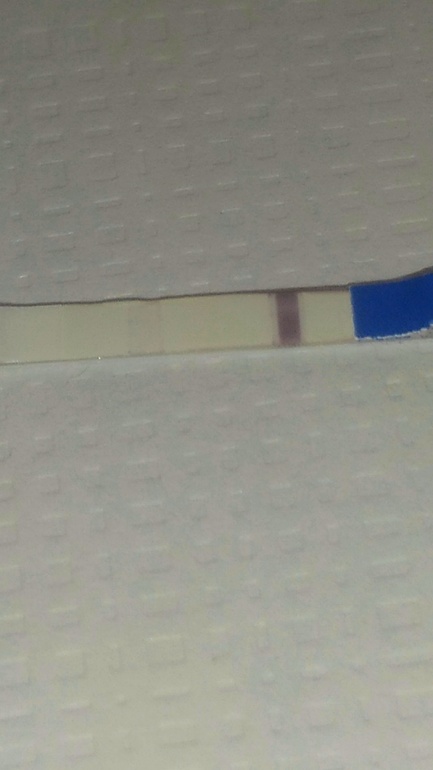

Добрый день. Сегодня 8 ДПО. Прибиралась в шкафчике,нашла тест леди чек ) ,решила замочить 😅 Какая-то широкая полоска и у контрольной по бокам еще полоски😲Вообще рано еще делать тесты или уже можно?

Добрый день. Сегодня 8 ДПО. Прибиралась в шкафчике,нашла тест леди чек ) ,решила замочить 😅 Какая-то широкая полоска и у контрольной по бокам еще полоски😲Вообще рано еще делать тесты или уже можно?